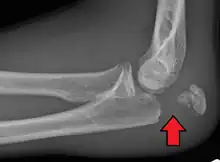

Powerful pull of the triceps muscle can also cause avulsion fractures.

To assess an olecranon fracture, a careful skin exam is performed to ensure there is no open fracture. Then a complete neurological exam of the upper limb should be documented.[5][2] Frontal and lateral X-ray views of the elbow are typically done to investigate the possibility of an olecranon fracture.[1] A true lateral x-ray is essential to determine the fracture pattern, degree of displacement, comminution, and the degree of articular involvement.

Tension band fixation is the most common form of internal fixation used for non-comminuted olecranon fractures.[5] It is typically reserved for noncomminuted fractures that are proximal to the coronoid.[2] This procedure is performed using Kirschner wire (K-wires) which converts tensile forces into compressive force.[2]